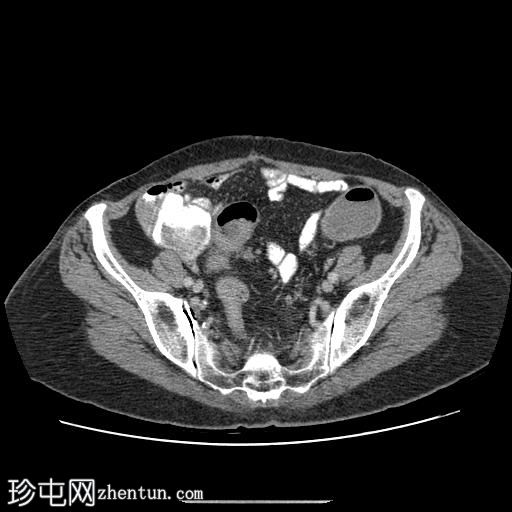

CT

轴位增强扫描

延迟期

口服造影剂

冠状位增强扫描

乙状结肠可见一段环周壁增厚伴管腔狭窄,伴有明显的结肠周围血管增生和一肿大的结肠周围淋巴结,最大直径为4mm。

未发现实体器官转移。

左肾中下极可见一约10mm的皮质囊肿。

病例讨论

这是一例经

病理

证实的T3N1aM0乙状结肠癌病例,根据TNM结肠癌分期系统或Dukes结直肠癌分期系统,该患者为65岁女性,分期为Dukes C期。